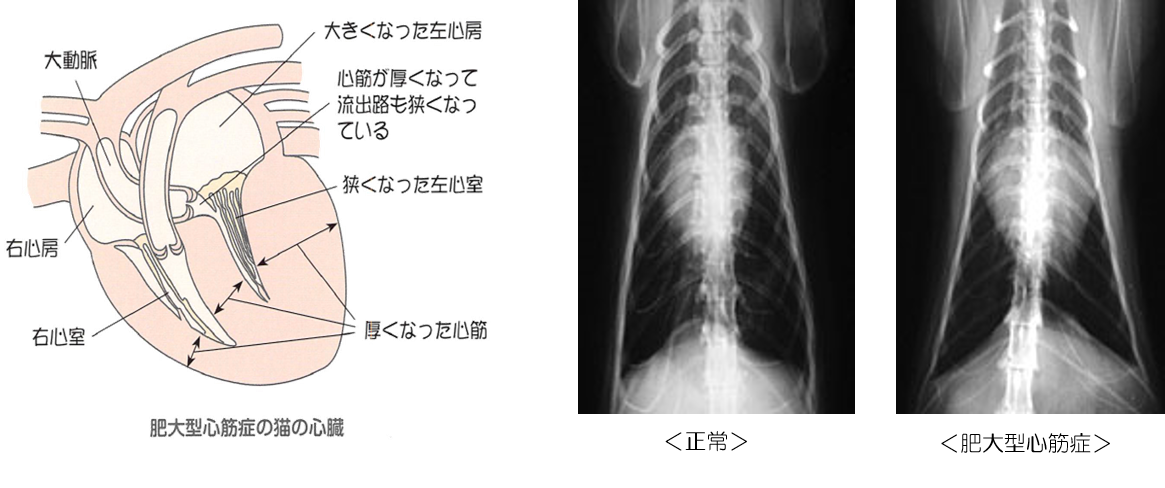

HOT ! 症例に学ぶ 肥大型心筋症 大型本(大型本) 心エコー解説 ~肥大型心筋症を診る~【第10回】症例紹介①

心エコー解説 ~肥大型心筋症を診る~【第10回】症例紹介①。肥大型心筋症専門外来|日本医科大学付属病院。肥大型心筋症専門外来|患者様のご紹介|医師・医療関係者へのご。

• 心エコー解説 ~肥大型心筋症を診る~【第10回】症例紹介①

• 肥大型心筋症専門外来|日本医科大学付属病院

• 肥大型心筋症専門外来|患者様のご紹介|医師・医療関係者へのご

• ひとことで言うと… #498|肥大型心筋症 | かんテキ | メディカ